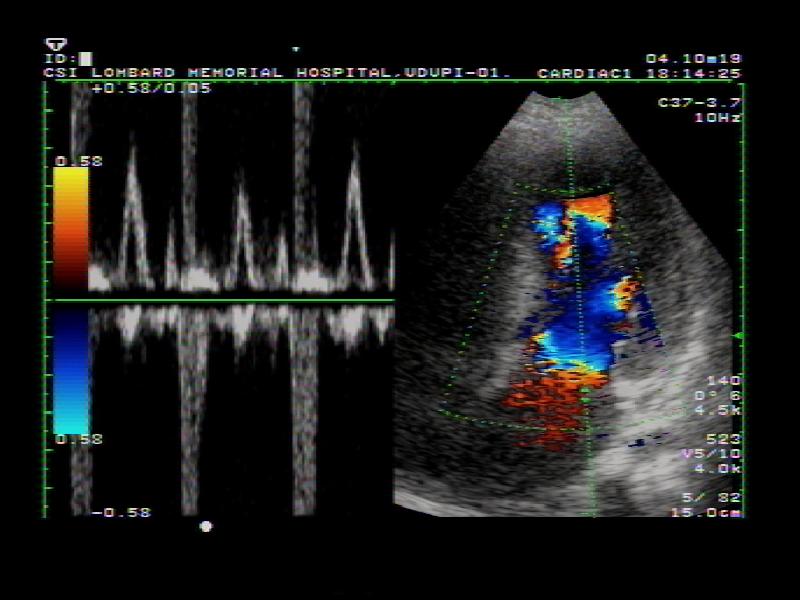

۳.اکوکاردیوگرافی داپلر (Doppler)

اکوکاردیوگرافی داپلر برای ارزیابی جریان خون در قلب و عروق جنین استفاده میشود. این روش برخلاف دو نوع قبلی که تمرکز بر ساختارهای فیزیکی قلب دارند، بیشتر به بررسی عملکرد قلب از نظر جریان خون میپردازد.

در این نوع تصویربرداری، پزشک میتواند سرعت و جهت جریان خون را اندازهگیری کند. این اطلاعات نقش کلیدی در تشخیص مشکلاتی مانند نارسایی قلبی، تنگی یا نارسایی دریچهها، و اختلالات در دهلیزها و بطنها دارد. در صورتی که پزشک به وجود ناهنجاری در گردش خون جنین مشکوک شود، استفاده از اکو داپلر بهعنوان ابزار تشخیصی الزامی خواهد بود.

اکوکاردیوگرافی داپلر: این تکنیک داپلر برای اندازه گیری و ارزیابی جریان خون از طریق اتاقک ها و دریچه های قلب استفاده می شود. داپلر همچنین میتواند جریان خون غیرطبیعی در قلب را تشخیص دهد که میتواند مشکلاتی مانند باز شدن بین حفرههای قلب، مشکل یک یا چند دریچه از چهار دریچه قلب یا مشکل دیوارههای قلب را نشان دهد.

داپلر رنگی داپلر رنگی شکل پیشرفته اکوکاردیوگرافی داپلر است. با داپلر رنگی، از رنگ های مختلف برای تعیین جهت جریان خون استفاده می شود. این کار تفسیر تصاویر داپلر را ساده می کند.